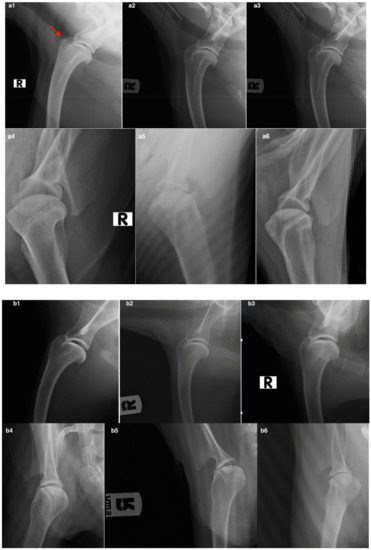

2.9. Radiographic Examination

3.2.3. Radiographic Assessment